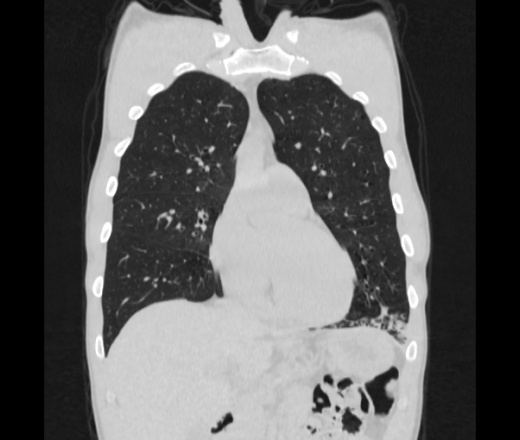

Мужчина пенсионного возраста. Цель назначения КТ ислючение зла в левом легком. Вижу тракционные бронхоэктазы с рубцовой эмфиземой по периферии, скорее всего БЭБ в стадии обострения. Дивертикулы трахеи. Выложил из за того что есть доля сомнения в отношении исключения зно3, немного смущают линии похожие на Керли.